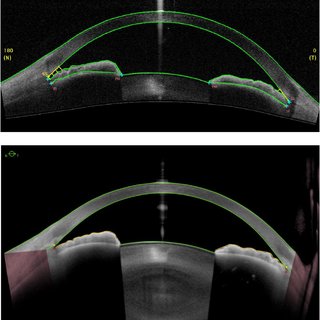

<UBM으로 관찰한 전안부 소견들>

CCT, Central corneal thickness, 중심각막두께를 초음파를 통해 직접 계산할수 있습니다.

전방의 깊이 Anterior chamber depth, ACD를 측정함에 있어 UBM은 각막내피에서부터 수정체 앞면까지를 계산해줌으로써, 실제 전방의 깊이를 볼수 있습니다.

공막돌기 Scleral spur 는 UBM을 볼 때 가장 중요한 표지가되는 구조입니다.

섬모체의 가장 앞부분이 부착되어 있고, 약간 돌출된 모양으로 되어 있어,

전방각 주위의 구조를 측정할 때 기준점이 됩니다.

공막돌기에서부터 500um(0.5mm) 떨어져져서 전방의 깊이를 측정하면 전방각이 열려있는 정도를 객관적으로 수치화하여 측정할수 있습니다.

이를 Angle opening distance로 약어로 AOD 500 이라합니다.

같의 의미로 250um (0.25mm)떨어진 상태에서 측정하면 AOD250 이라고하기도합니다.

Trabecular-iris angle (TIA) 라는 것은 AOD 500을 측정하기위한 지점과 홍채가 이루는 각도를 의미합니다.

TISA :Trabecular iris surface area 라는 것은

공막돌기에서 500um 떨어진 지점(AOD500을 측정하기위한 지점) 에서 그은 가상의 선과,

공막돌기에서 그은 가상의 선 사이의 면적을 의미합니다.

ARA Angle recess area 라는 것은 공막돌기에서부터 500um 혹은 750 um 떨어진 곳에서부터의 전방각의 면적을 측청한 것입니다.

ARA 500 이라하면 공막극에서 500 um 떨어진곳에서부터 가상의 직선과, 각막내피, 섬유주, 홍채에 의해 둘러싸인 공간의 면적입니다

공막돌기에서 500um 떨어져서 섬유주(Trabecular meshwork, TM)에서부터 Iris를 넘어서 Ciliary process 까지의 거리를 TCPD, Trabecular ciliary process distance 라고합니다.